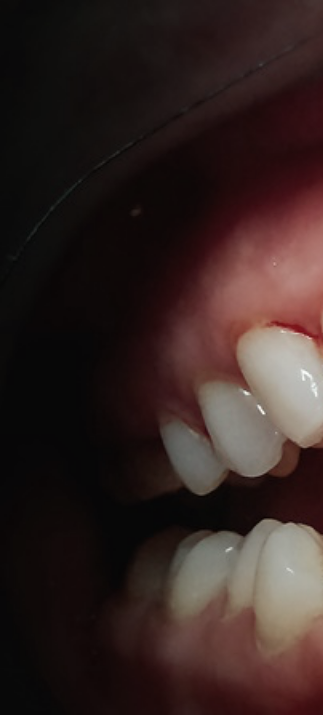

두번째 증상은 잇몸이 붉게 변하며

붓기가 생기는것인데요.

건강한 잇몸은 연분홍색을 띄며,

잇몸에 염증이 발생하면 빨갛게

부워오르게 된다고 했어요.

이러한 경우 잇몸이 예민해져 있어

살짝만 칫솔로 건드려도 출혈이 쉽게

발생하며 통증 또한 느껴질 수 있는

부정적인 상태에 해당됐어요.